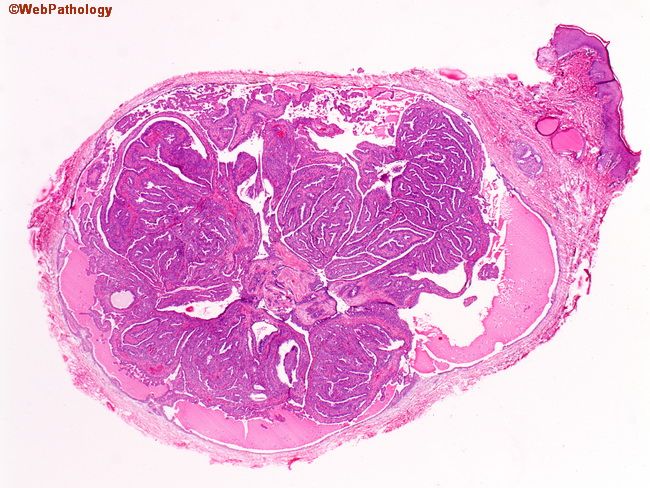

Патолоджи аутлайн

Патолоджи аутлайн 113 фото